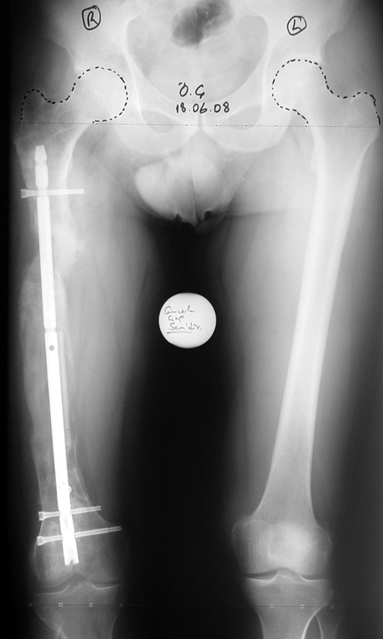

Eksternal fiksatör ile geçen süre (eksternal fiksasyon indeksi), gereken distraksiyon miktarına bağlıdır ve bu süre boyunca bazı komplikasyonlarla karşılaşılabilir. Distraksiyon dönemi sona erdikten sonra, distraksiyon süresinin iki katını aşan konsolidasyon döneminde hastalar eksternal fiksatörü zorlukla tolere edebilirler. Yeterli konsolidasyon sağlanmadan eksternal fiksatör çıkartılırsa ise kırıklar, deformite ve kısalık oluşabilir. Hastanın fiksatör ile birlikte geçirdiği sürenin azaltılması ve böylece hasta konforunun ve aktivite düzeyinin arttırılması için intramedüller çivi üzerinden uzatma yöntemi uygulanmaktadır. Bu yöntemde distraksiyon dönemi sona erdiğinde kemiğin içindeki çivi statik olarak kilitlenmekte ve eksternal fiksatör çıkartılmaktadır. Stabilizasyon intramedüller çivi tarafından sağlandıktan sonra konsolidasyon dönemi gerçekleşmektedir. Bu şekilde hem eksternal fiksatörün uzun süre kalmasından hem de erken çıkartılmasından kaynaklanan komplikasyonların önüne geçilmektedir.

Vaka 1

Vaka 2

Vaka 3